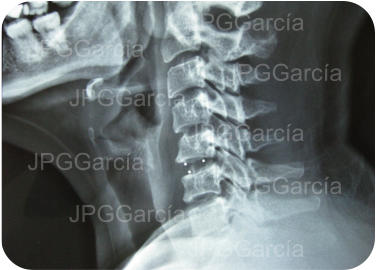

EXTRUSIÓN DE DISCO CERVICAL C4-C5